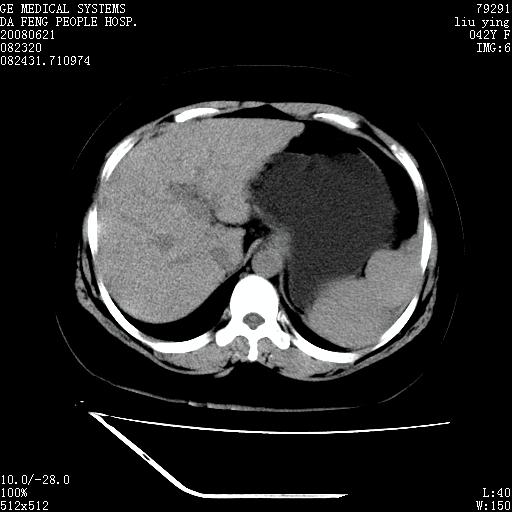

标题: CT14225:女性46岁。当地B超示肝内占位,来我院作CT检查。请 [打印本页]

标题: CT14225:女性46岁。当地B超示肝内占位,来我院作CT检查。请

右叶肝癌灶;慢性胆囊炎,不除外占位;;副脾可能性

肝内结节强化特点符合原发性肝癌表现,脾脏改变考虑为增大及先天发育所致。

动脉期病原灶明显强化高于肝密度且中央有无强化区,静脉期强化程度下降明显,延迟低于肝密度,考虑肝腺瘤可能性大,

符合肝癌表现,脾脏大(肝硬化?)

肝内结节强化特点:快进快出符合原发性肝癌表现

非常典型,肝ca,脾脏先天性发育异常,脾大

此患者虽然符合快进的特点,却不符合快出的特点,因为门脉期几乎是等密度,不符合肝癌的增强表现,所以我考虑肝局灶性结节增生可能性大

肝内结节强化特点符合原发性肝癌表现。脾大。